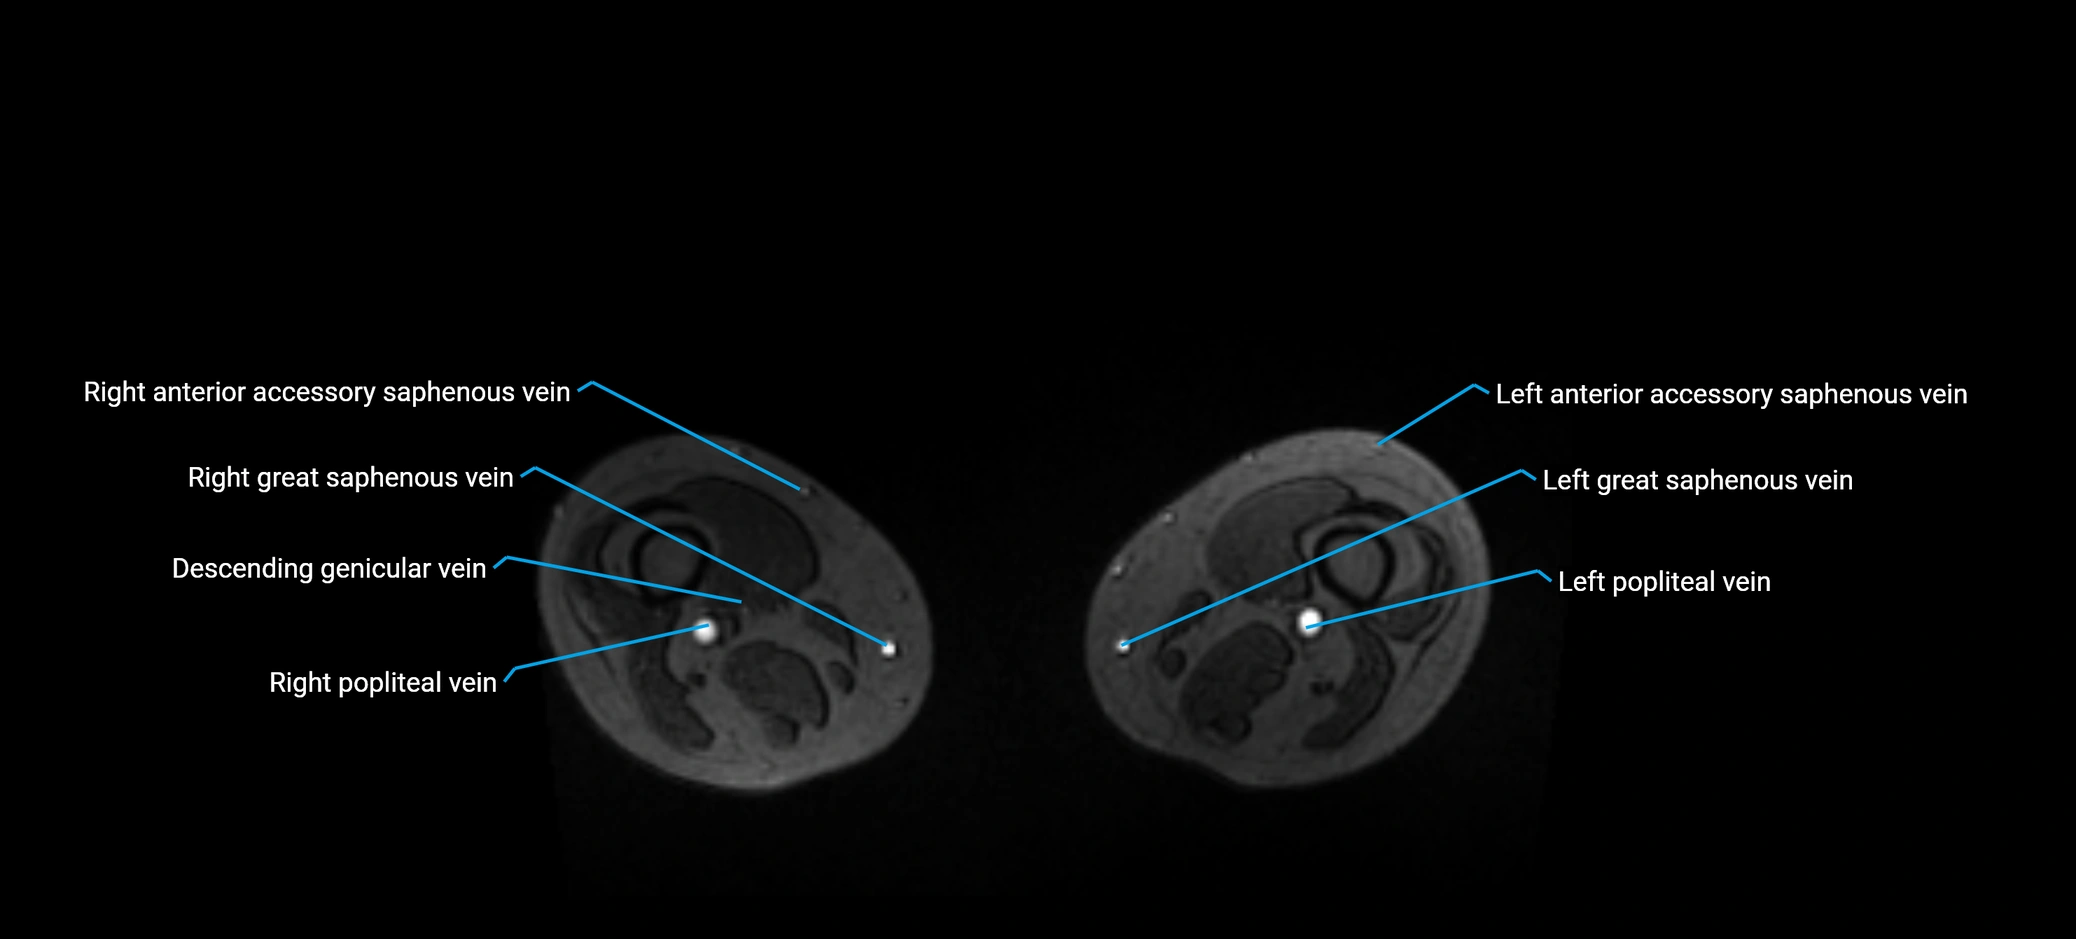

MRV TOF (Time-of-Flight MR Venography):

• Appears as a bright, high-signal vascular channel representing flowing blood

• Clearly shows branching pattern of right portal vein into anterior and posterior branches

• Best in coronal or axial reconstructions for segmental mapping

• No need for contrast, relies on flow-related enhancement